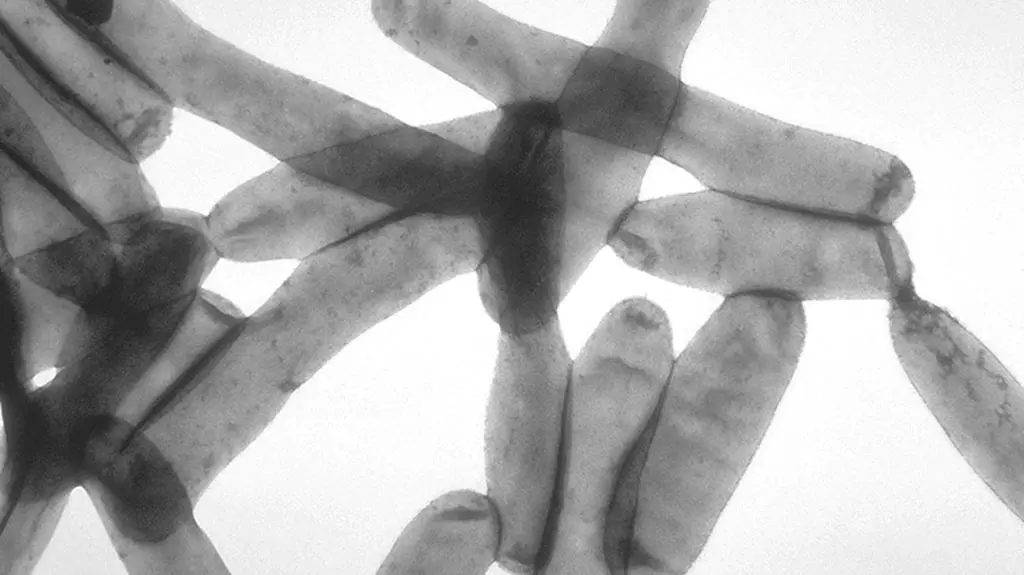

- Bakterie Legionella pneumophila wykryto w efekcie rutynowego badania sanepidu w oddzielnej, obecnie remontowanej części budynku - poinformował we wtorek PAP rzecznik Wojewódzkiego Szpitala Specjalistycznego w Legnicy Krzysztof Maciejak.

Tylko w jednym kranie. W części, gdzie nie leczono pacjentów

- Bakterie wykryto tylko w jednym kranie. Pozostałe próbki są wolne od legionelli, ale placówka wykonuje termiczne odkażanie sieci wodociągowej. W tej części w ogóle nie odbywało się leczenie, choć wcześniej był to oddział paliatywny. Nie ma w szpitalu pacjentów zakażonych - powiedział Maciejak. Na Podkarpaciu zmarło 14 osób zakażonych bakterią Legionella pneumophila, wszystkie miały choroby współistniejące - poinformował we wtorek rzeszowski sanepid. Dotychczas zakażenie bakterią potwierdzono w tym regionie u ponad 150 osób.